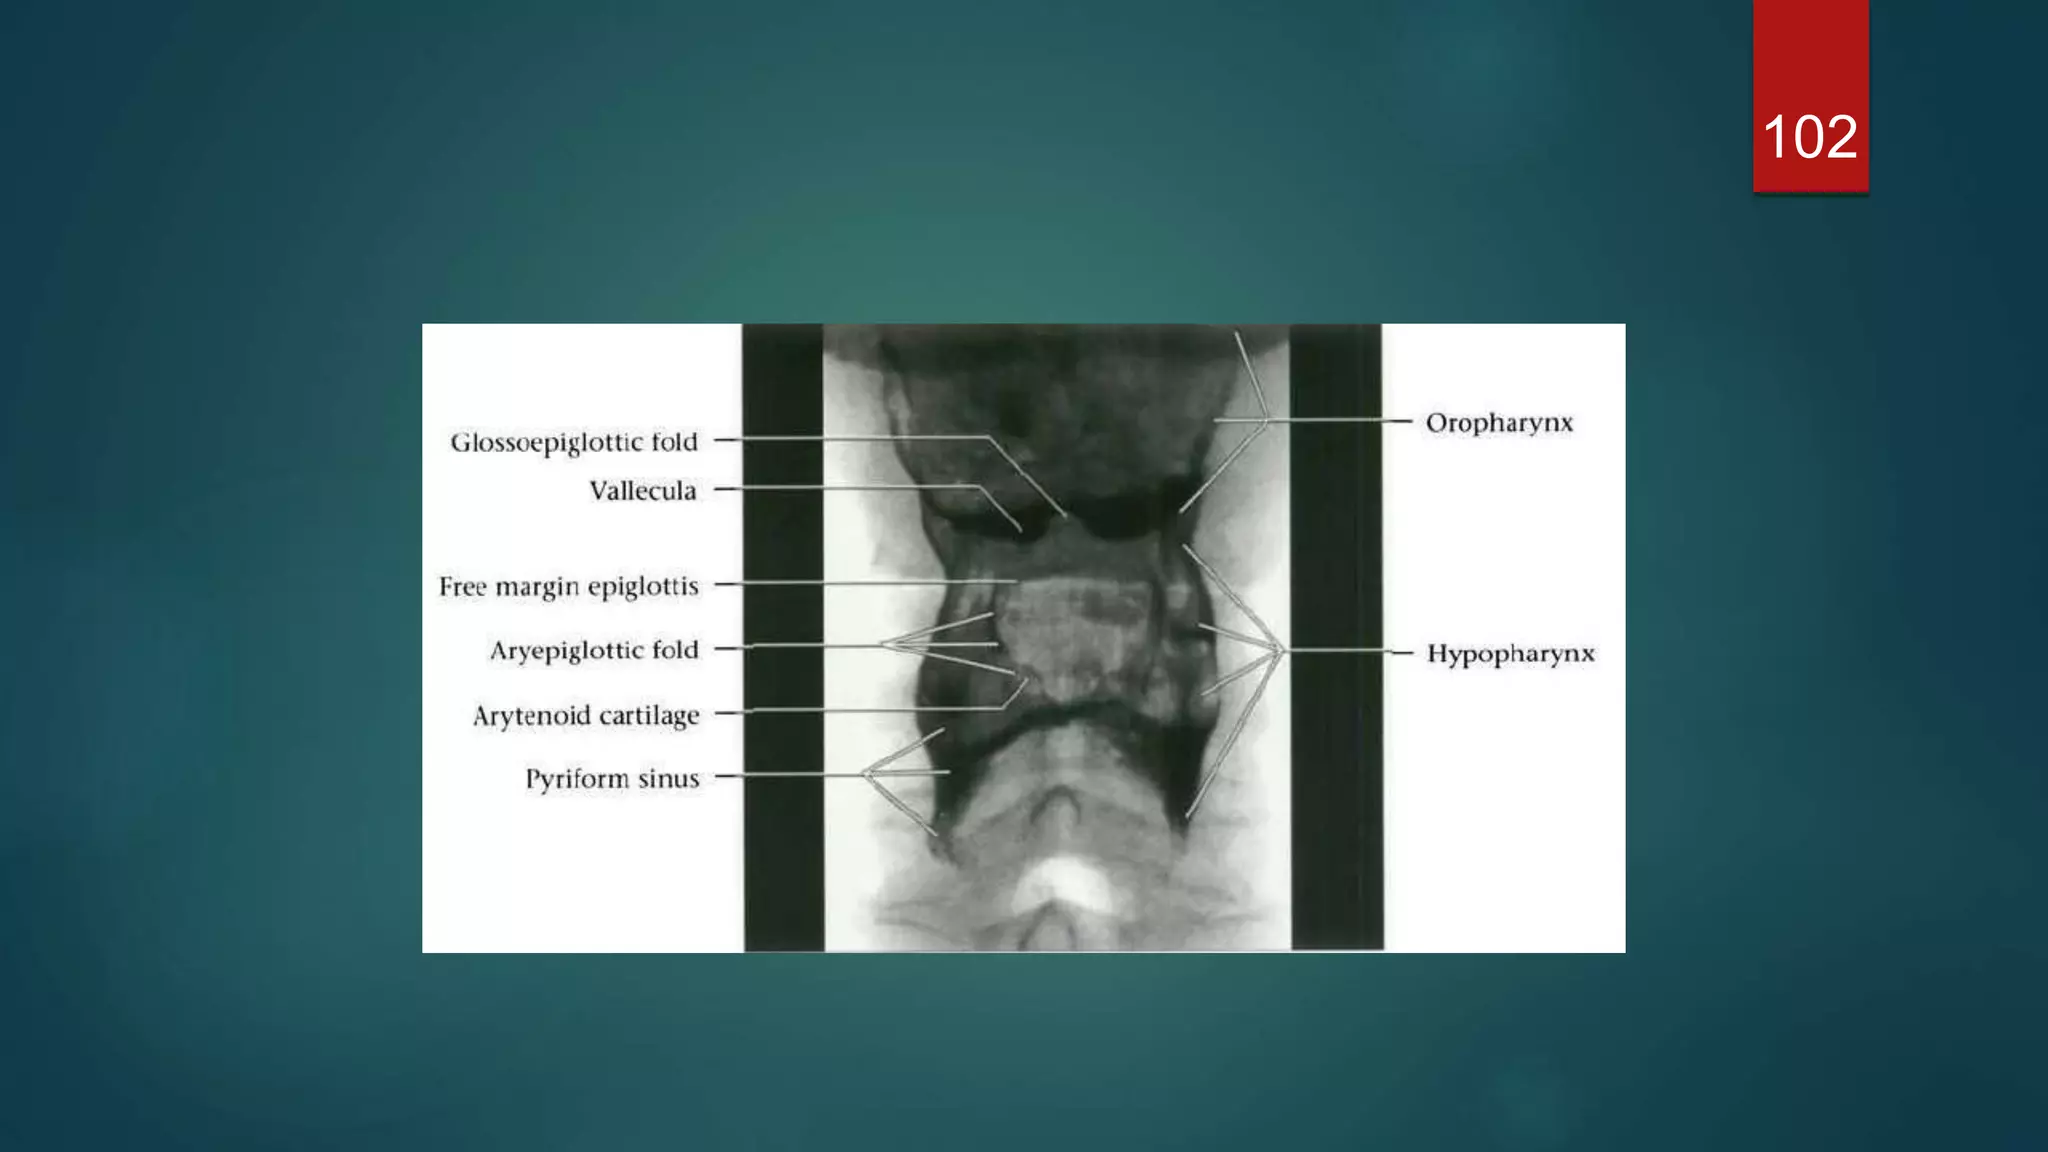

 Three mucosal folds, the glossoepiglottic folds - namely, a

central and two lateral folds - pass from the anterior surface of

the epiglottis to the base of the tongue. These form paired

recesses between the base of the tongue and the epiglottis

known as the valleculae.

 A further pair of mucosal folds pass from the lateral margin of the

epiglottis posteriorly to the arytenoid cartilages separating the

larynx from the piriform fossae. These are the aryepiglottic folds

which, together with the epiglottis, define the entrance to the

larynx.

 The epiglottisis a leaf-shaped cartilage whose narrow base is attached to the inner surface of the thyroid cartilage  It projects up behind the base of the tongue and directs boluses laterally into the piriform fossae during deglutition, thus protecting the larynx.  Three mucosal folds, the glossoepiglottic folds - namely, a central and two lateral folds - pass from the anterior surface of the epiglottis to the base of the tongue. These form paired recesses between the base of the tongue and the epiglottis known as the valleculae.  A further pair of mucosal folds pass from the lateral margin of the epiglottis posteriorly to the arytenoid cartilages separating the larynx from the piriform fossae. These are the aryepiglottic folds which, together with the epiglottis, define the entrance to the larynx.  The cavity of the larynx is divided into three parts by upper and lower pairs of mucosal folds. The upper pair of folds are the false cords. The space between the laryngeal entrance and the false cords is known as the vestibule or the sinus of the larynx.  The lower pair of folds are the true cords and contain the vocal ligaments, which are responsible for voice production. The space between the false and true vocal cords is the laryngeal ventricle. 70